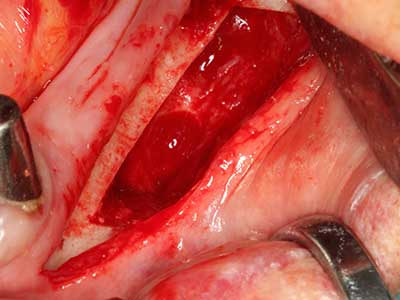

La piezochirurgia presenta altri vantaggi per quanto riguarda la raccolta di blocchi ossei. Oltre all'elevata precisione dell'osteotomia appena descritta, l'utilizzo di puntine per sega molto sottili permette di minimizzare in maniera significativa la perdita di materiale. È molto probabile che si verifichi una maggiore perdita di materiale durante la raccolta utilizzando puntine di strumenti più spessi, in particolare delle frese Lindemann (Lakshmiganthan, Gokulanathan et al. 2012). La separazione basale, necessaria in particolare per i trapianti di blocchi nella zona retromolare, viene semplificata grazie a seghe specificatamente progettate di forma rettangolare; di conseguenza la piezochirurgia è considerata una procedura precisa, semplice e sicura per la raccolta di blocchi di osso nella zona retromolare (Happe 2007) (figg. 1-12).

Il tessuto osseo non è semplicemente una struttura minerale, ma contiene anche una percentuale significativa di fibre di collagene. Ciò significa che non possiede solo una buona forza di compressione, ma anche un certo livello di flessibilità che è possibile sfruttare durante l'esecuzione degli accrescimenti di osso. Nella procedura di espansione classica con incisione ossea, la cresta alveolare atrofizzata viene incisa longitudinalmente ed espansa con cautela dopo aver raggiunto una profondità di osteotomia adeguata (figg. 13-16), idealmente senza una sostanziale rimozione del periostio (Brugnami, Caiazzo et al. 2014, Stricker, Fleiner et al. 2014). I sistemi a piastra e vite con distanza di espansione incrementale si sono dimostrati efficaci nella separazione delle due lamelle ossee restando al di sotto della soglia di frattura. In generale, sono richieste larghezze dell'osso residuo di almeno 3-4 mm (Chiapasco, Zaniboni et al. 2006) per garantire un'adeguata flessibilità e una copertura sufficiente dell'osso per gli impianti futuri. Se necessario, un'osteotomia di rilascio verticale su uno o più lati può migliorare la flessibilità. Una combinazione con ulteriori tecniche di accrescimento, in particolare dal lato buccale, è stata descritta come un'alternativa alla tecnica classica.

La procedura di incisione è particolarmente atraumatica e non comporta una perdita significativa di dimensione durante l'utilizzo delle seghe piezoelettriche, così come non si notano differenze rilevanti tra impianti in mandibole incise e impianti in una cresta alveolare senza deficit osseo (Chiapasco, Zaniboni et al. 2006, Danza, Guidi et al. 2009). Una sufficiente irrigazione continua è essenziale, tuttavia, in particolare con incisione profonda e localmente ristretta, per prevenire la sollecitazione termica nelle regioni apicali dell'osteotomia.